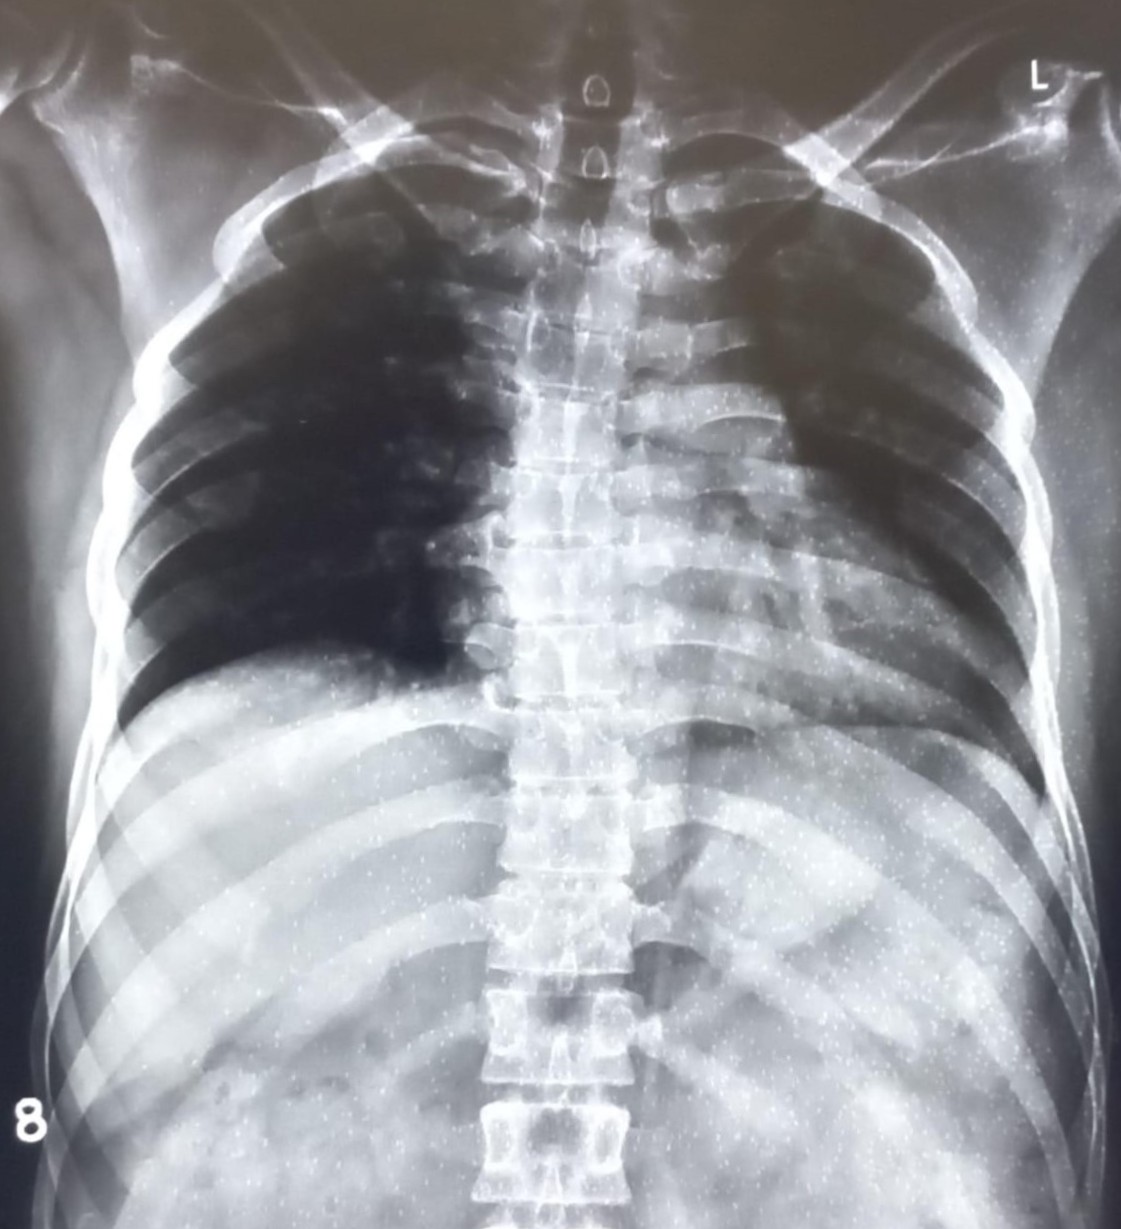

| 4404 | IGGMC, Nagpur, Nagpur | P2 | 29-68 | Gauri Rathod | Consent taken on Paper | 12 Yrs. |

Provisional Diag : Lower Respiratory Tract Infection

Final Diag : LEFT LOWER ZONE INFILTRATIONS |

Non-TB Case (Confirmed) | Left Mid Zone Radiopacity/ clothing Artifact | Abnormality visible on x-ray |